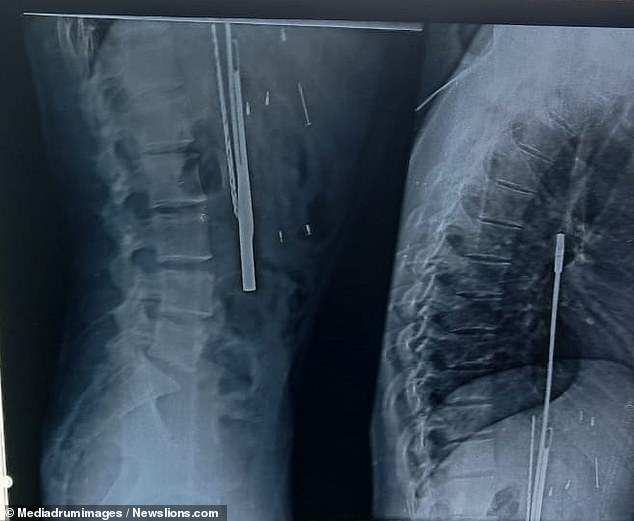

They were stunned to find objects such as a knife, screwdriver, razor blades and plastic items inside Mr Thakur's stomach.